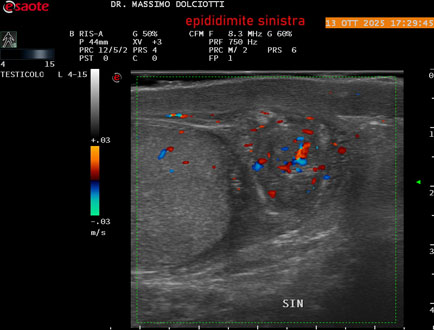

Data inserimento: 14/10/2025

Ecografia del: 13/10/2025

Strumento: Esaote MyLab Eight

Sonda: Lineare Multifrequenza 4-15 MHz

Età Paziente: M 70 anni

Motivazione dell'esame: da 2 giorni dolore al testicolo sinistro.

Commento all'esame: le immagini ed il video documentano l'epididimo sinistro spiccatamente aumentato di volume e di vascolarizzazione, come da flogosi. Didimo sinistro lievemente aumentato di volume. Quadro clinico ed ecografico da ricondurre ad epididimite acuta sinistra.

Conclusioni: epididimite acuta sinistra (acute left epididymitis).

Presentazione: Dr. Massimo Dolciotti - Ancona

Elaborazione digitale: Andrea Dini - Ancona